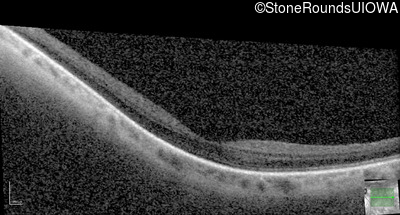

Optical Coherence Tomography - Right - 20/40 +2

Exemplar / OCT Stack